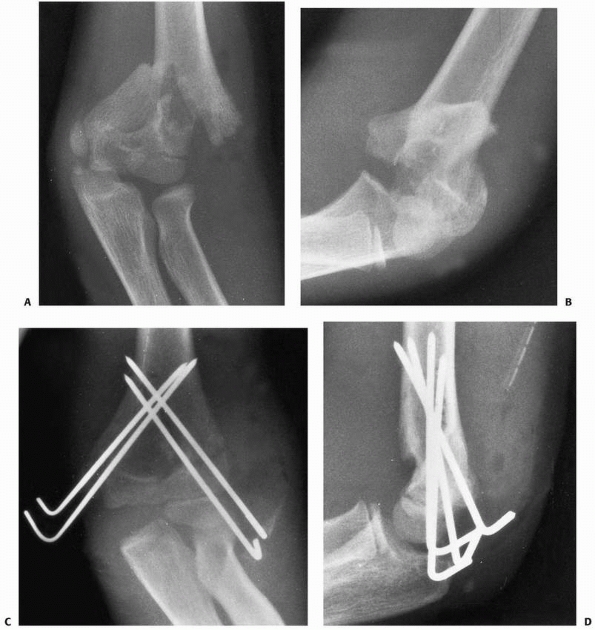

![]() |

FIGURE 15-27 A,B. Fracture of the capitellum in a 14-year-old boy. C,D. After open reduction and fixation with two small cannulated screws through a lateral approach.

|

if an anatomic reduction can be achieved with a minimum of open

manipulation or dissection, then we prefer to reattach it with two

small cannulated screws inserted from posterior to anterior through a

lateral approach. Enough bone must be present in the capitellar

fragment to engage the screw threads, and if possible, countersink the

heads of the screws (see Fig. 15-27). If the